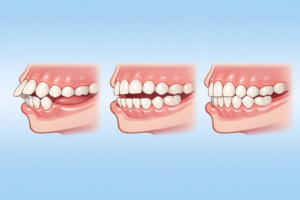

長期間の指しゃぶりは、歯や顎に継続的な力がかかるため、次のような問題が起こることがあります。

・出っ歯(上顎前突)

・前歯が噛み合わない(開咬)

・歯列が狭くなる

実際に、指しゃぶりの圧力によって歯の位置が変わり、噛み合わせが乱れることが報告されています